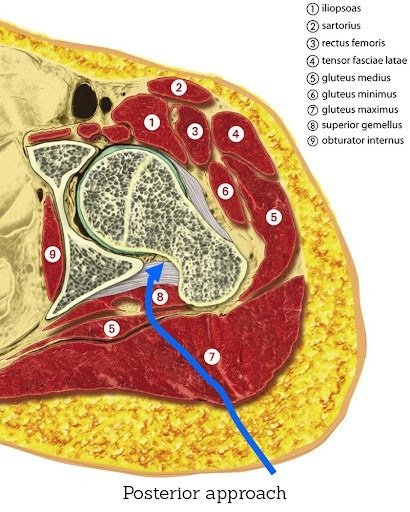

Dr Hockings is experienced in multiple approaches, including the anterior approach, posterior approach, and bikini incision techniques. Each method provides specific advantages in terms of exposure, soft tissue handling, and incision placement.

The posterior approach accesses the joint from the back of the hip and remains a well-established and widely used technique. It provides excellent visibility of the joint, which is especially useful when dealing with:

Although the posterior approach involves releasing some muscles and soft tissue, these are repaired during closure. With the right surgical technique and rehabilitation, long-term outcomes remain excellent.

If your surgery was performed using a posterior approach, the hip joint was accessed from the back, which requires more protection of the posterior structures during healing.